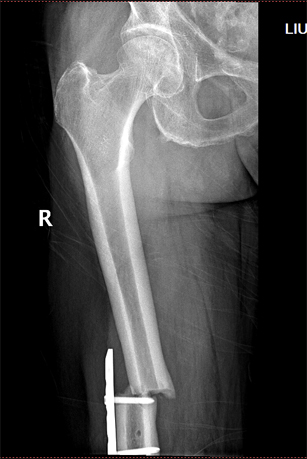

术前影像

患者刘先生,2017年1月在外院行“右侧全膝关节置换术”,术后4个月不慎摔伤致右股骨髁上骨折,骨折移位,在我院关节外科-创伤骨科成功行骨折复位钢板内固定术,术后恢复良好。今年4月不慎再次摔伤,导致钢板近端骨折,骨折端成角、旋转移位。患者及家属出于对我院整体实力的信任,再次入住我院关节外科-创伤骨科。